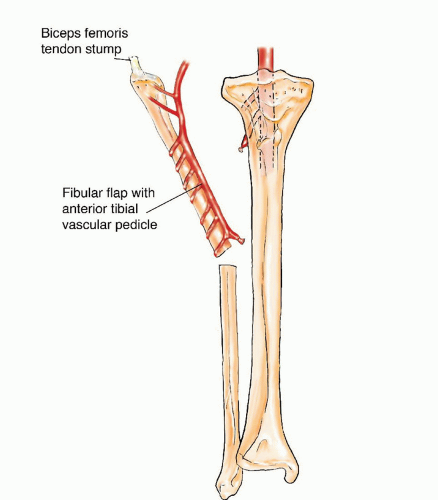

Free Vascularized Fibular Grafting—25 Years’ Experience: Tips …

Vascularized fibula bone graft to reconstruct bone defect in the …

Free Fibular Flap | Musculoskeletal Key

The Use of Free Vascularized Fibular Grafts for Reconstruction of …

The Use of Free Vascularized Fibular Grafts for Reconstruction of …